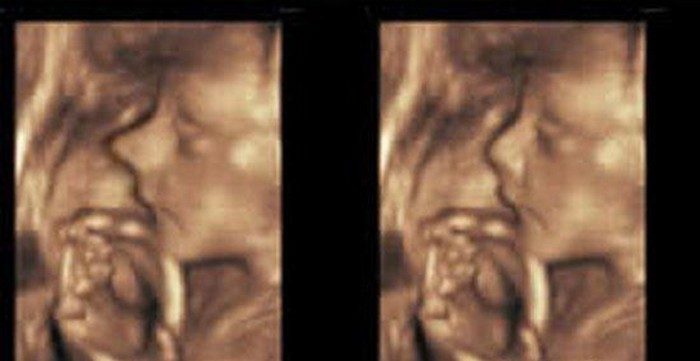

В качестве примера можно привести случай, произошедший несколько лет назад в Беверли Хиллз. Беременная мать обратилась к пластическим хирургам с просьбой сделать операцию ее еще не родившемуся сыну. Ведь ультразвуковое исследование плода показало, что мальчик, судя по всему, унаследует ужасно длинный нос от своего родителя. Так почему бы не избавить ребенка от этого уродства в самом раннем возрасте?

Интересно, что врачи после определенных раздумий согласились провести данную операцию. Они решили, что питательная среда в утробе матери позитивно повлияет на шрамы после хирургического вмешательства, и к моменту рождения ребенка от них не останется никаких следов.

Операция прошла успешно.